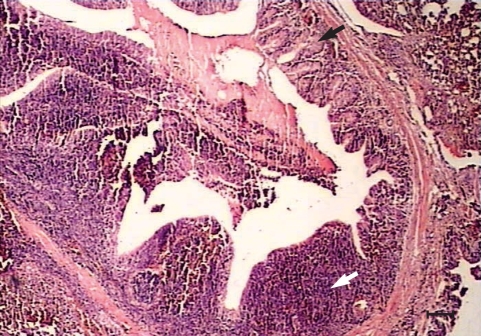

Histopathological changes were observed in organs of all the experimentally infected chickens at day 240 PI. Peribronchiolitis with infiltration of lymphocytes, and hyperplasia of bronchiolar associated lymphatic tissues (BALT) and goblet cells, were evident in the lungs of infected chickens (

Fig. 1). Mild hemorrhages, lymphocytic infiltrations, and a few eosinophils were observed in the meninges, especially over the cerebellum (

Fig. 1Peribronchiolitis, hyperplasia of the bronchiolar associated lymphatic tissues (white arrow) and goblet cells (black arrow) in the parenchyma of the lungs from a chicken infected with 1,000 Toxocara cati eggs on day 240 PI. H-E stain. Scale bar = 135 µm).